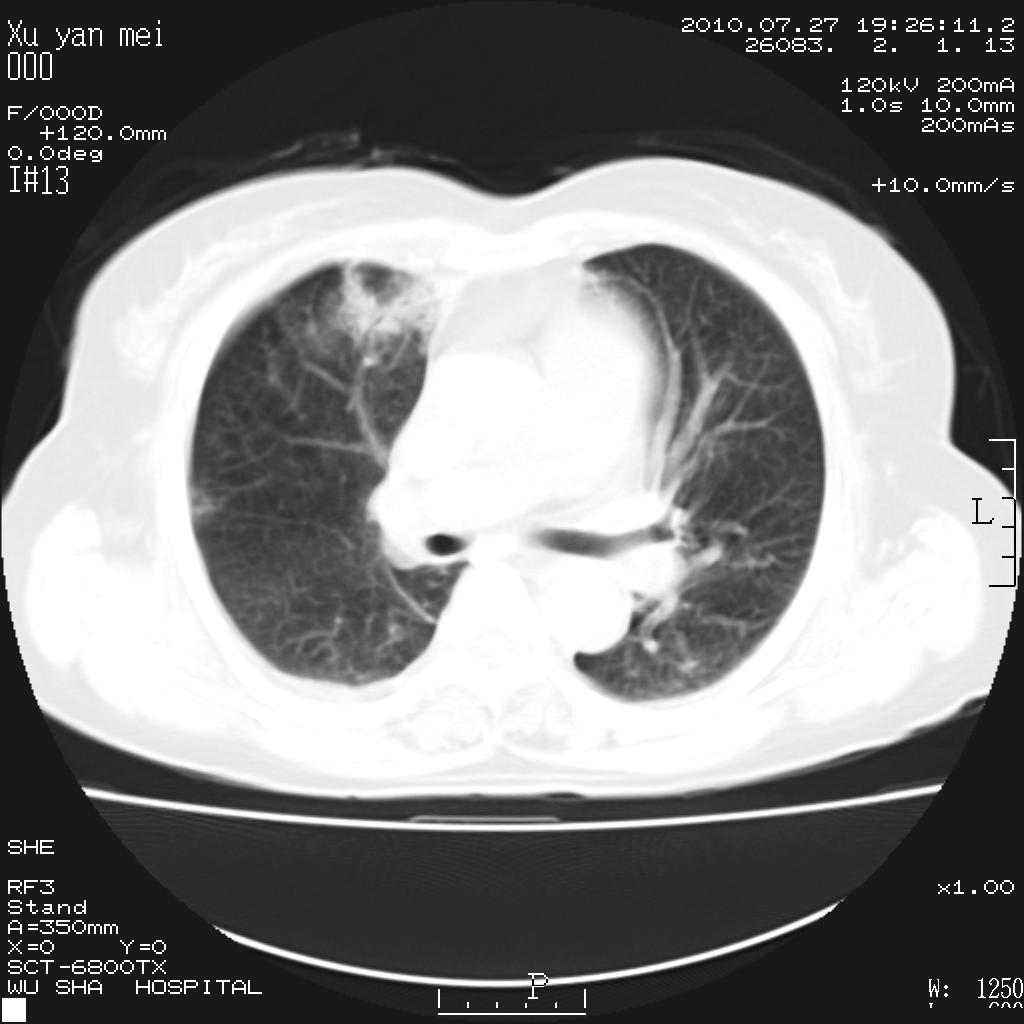

女,60岁,胸痛就诊,右肺结核?炎症?其它?(胸片右侧中上肺野确实看不到什么啊)

1)考虑两肺感染性病变;建议抗炎治疗后复查。2)双侧少量胸腔积液。

1)考虑两肺感染性病变;建议抗炎治疗后复查。2)右侧少量胸腔积液。

双肺炎症可能性大,建议抗炎后复查。右侧胸腔少量积液。双侧胸膜轻度增厚。

考虑两肺感染性病变;不除外肺栓;建议抗炎治疗后复查。